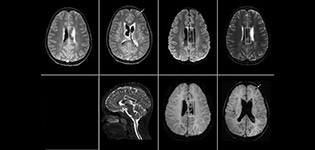

SWIp unterstützt die Diagnosesicherheit bei Schädel-Hirn-Traumata

Der Nutzen suszeptibilitätsgewichteter Bildgebung bei der Darstellung von Gehirnverletzungen ist gut dokumentiert. Das Multi-Echo-SWIp-Verfahren von Philips liefert eine schnelle, suszeptibilitätsgewichtete Bildgebung mit verbessertem Suszeptibilitätskontrast und hoher Auflösung.

„Die pädiatrische Bildgebung stellt uns durchaus vor Herausforderungen“, sagt Dr. Miller. „Da unsere Patienten häufig sehr klein sind, benötigen wir eine Bildgebung mit hoher Auflösung. Bei Gehirnverletzungen benötigen wir schnell Informationen, damit das Klinikteam die erforderlichen Entscheidungen treffen kann. Wir sind auf eine hohe Auflösung und robuste Bildgebungskapazitäten angewiesen – Merkmale, die SWIp bereitstellt.“

„SWIp hilft uns bei der Erkennung von Blut oder Blutkomponenten, Kalzifizierung und Erkrankungen des Gefäßsystems“, führt Dr. Miller aus. „Bei Kindern mit Schädel-Hirn-Traumata werden die verletzten Bereiche hervorgehoben, und zwar besser als mit einigen der Verfahren, die wir früher angewendet haben. Diese Kinder weisen häufig Mikroverletzungen auf, die zu kleinen Blutungen oder Gewebeläsionen führen. Mit Hilfe von SWIp können wir das Ausmaß und die Art der Verletzung besser beurteilen. Die optimale Charakterisierung einer Verletzung unterstützt die diagnostische Sicherheit.“

Vollständige Übernahme nach anfänglichem Vergleich

„Ich würde anderen Benutzern die Implementierung von SWIp definitiv empfehlen. Wir fügten die SWIp-Sequenz anfangs hinzu, weil deren Einsatz in der Literatur sehr positiv bewertet wurde. Dann verglichen wir SWIp direkt mit den bei uns eingesetzten 2D-Gradientenechosequenzen. Nach einer Vielzahl von klinischen Erfahrungen, die den Nutzen belegten, entschieden wir uns, die alten Sequenzen durch SWIp zu ersetzen. Wir können damit die pathologischen Prozesse im Gehirn besser beurteilen, die bei unseren bisherigen Bildgebungssequenzen weniger offensichtlich waren“, erklärt Dr. Miller. „SWIp ist mittlerweile eine Routinesequenz für die Bildgebung bei Patienten mit Schädel-Hirn-Traumata am PCH, und sie wird episodisch auch bei Patienten eingesetzt, die intrakranielle Gefäßveränderungen aufweisen.“

„Ich glaube, dass SWIp sich aufgrund der hohen Sensitivität für venöse Blutkomponenten rasch zum Bildgebungsstandard bei Schädel-Hirn-Traumata entwickeln wird. SWIp kann auch bei der Gewinnung von Patienten helfen. So bitten unsere Neurochirurgen häufig darum, dass die Patienten mit unseren Scannern untersucht werden, die über hochempfindliche Verfahren wie SWIp verfügen. SWI-Sequenzen werden zudem immer häufiger bei anderen Gefäßveränderungen angewendet, da sie Optionen zur physiologischen Beurteilung des Gehirns bieten, die über eine standardmäßige strukturelle Bildgebung hinausgehen.“